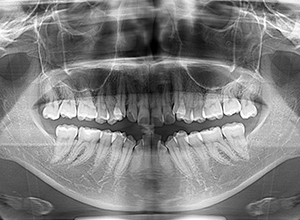

| パノラマ所見 | 上顎両側第三大臼歯は存在して挺出が認められた。 |

| セファロ所見 | 下顎枝、骨体部共に大きくしっかりとしており、バランスの良い形をしていた。上顎突出度は大きく、ANB6.0°と前後的にはⅡ級を呈していた。 |